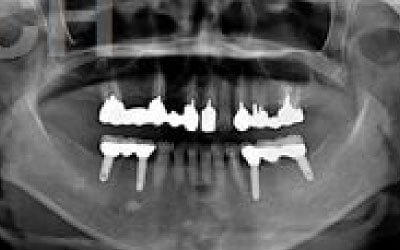

ブリッジとインプラントは、隣接する歯の寿命に大きな差があります。

ブリッジは支えの歯が虫歯でなくとも大きく削る必要があり、さらに噛む負担が1.5倍もかかるため寿命が短くなります。

統計ではブリッジの支えの歯は、10年以内に68%が抜歯になります。

ブリッジ治療でも、 失った歯にかかっていた力は残っている前後の歯が支えます。 結果的に、残っている歯には抜歯していないときの1.5〜2倍程度の力がかかるのです。

ブリッジなどの治療では前後の歯を大きく削る必要があります。場合によっては、虫歯でもないのに歯の神経をとることも。実は神経をとって被せ物をすると、歯は一気に最終ステージになってしまいます。

ブリッジとインプラントの大きな違いは、前後の歯の寿命に大きく関わることです。

ブリッジ治療では、抜けた歯の両隣を土台とするため、健康な歯でも大きく削る必要があり、負担がかかります。

また、失った歯の噛む力を前後の2本で支えるため、通常の約1.5倍の力がそれぞれにかかることになります。

1)ブリッジ治療

2)健康な隣の歯を大きく削る+支える歯に通常以上の力がかかる

3)結果として、両隣の歯の寿命が短くなる

実際に、支えとなる歯の約68%が10年以内に抜歯に至るというデータもあります。